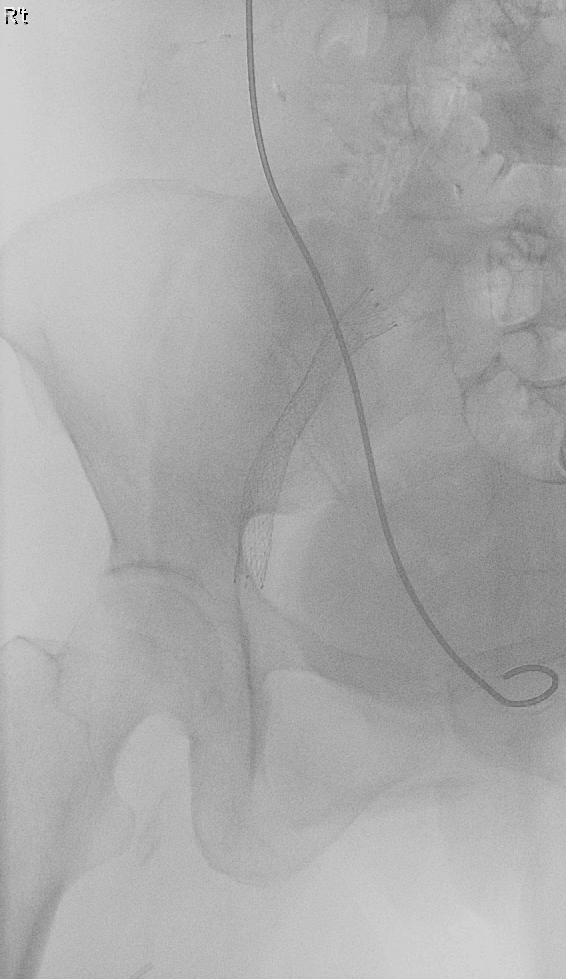

Deep Vein Thrombosis Due to Iliac Vein Compressed by Tumor 圖二 雙側股靜脈穿刺手術時導管穿不過去 圖三 順利從前脛靜脈進行CDT 圖四 放置髂靜脈支架後血流較通暢 返回 VTE Casebook